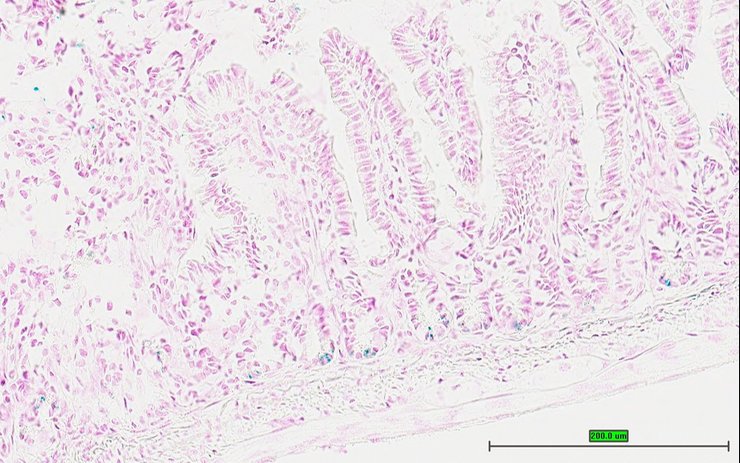

TS28: esophagus Present UC Davis_1875592

Specimen UC Davis_1875593: postnatal adult; Ghtm1.1(KOMP)Vlcg/Gh+ (more )